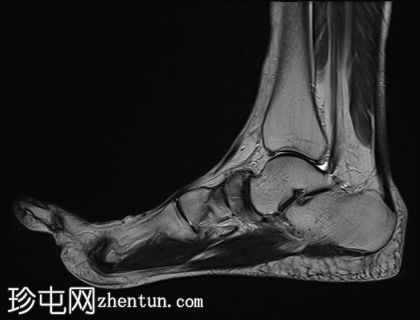

矢状面

PD 脂肪饱和度

舟骨呈二分状,分为两个骨块——较大的内侧骨块和较小的外侧骨块。

内侧骨折块外侧面呈“逗号状”,舟骨相对于距骨头轻微向内移位。

外侧骨折块及其外侧均呈斑片状T1低信号和PD FS高信号,并伴有硬化和微小囊肿,提示软骨联合/纤维界面存在慢性应激反应或退行性改变,可能伴有缺血性坏死。

双分舟骨区域外未见急性骨折线或骨髓水肿。

周围跗骨和关节未见明显异常。

未见明显软组织异常或关节积液。